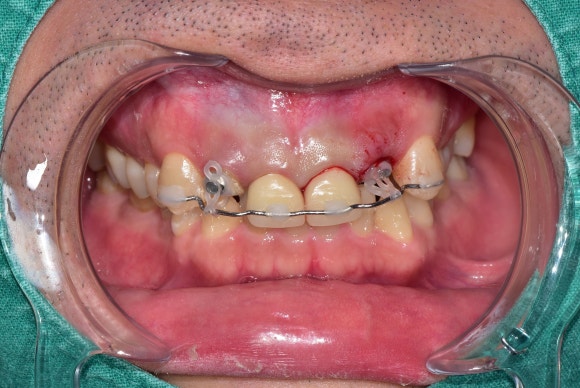

20250228

교정적정출술은 인접치아에 와이어를 붙이는 것에서 시작합니다.

꺼낼 치아에 고무줄을 연결합니다.

영차! 영차!